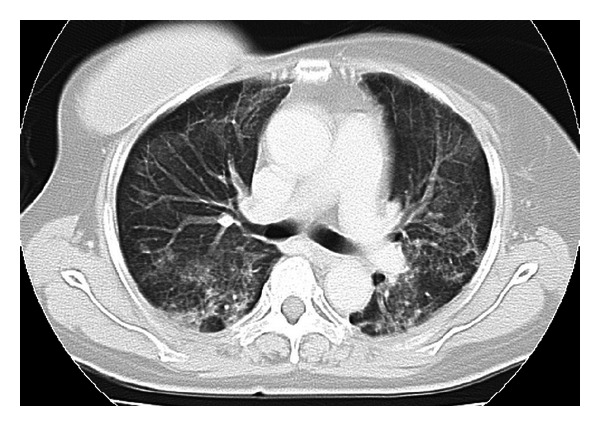

The patient was scheduled to receive six cycles of adjuvant chemotherapy, with each cycle comprising 5-Fluorouracil at 500 mg/m2, Epirubicin at 100 mg/m2, and Cyclophosphamide at 500 mg/m2 on day 1 within a 3-week period. The patient received 9.9 mg of intravenous dexamethasone on the day of chemotherapy and oral dexamethasone at 4 mg twice daily for 3 days after chemotherapy administration. The patient presented to our hospital due to fever and general fatigue 14 days after completing the third course of chemotherapy with FEC. Laboratory studies revealed a white blood cell count of 700/mm3, with 59% neutrophils. The patient was admitted for febrile neutropenia and intravenous cefepime dihydrochloride was commenced at 2.0 g two times daily. Granulocyte colony stimulating factor (G-CSF) therapy was also administered on hospital day 0 (Nartograstim 50 μg subcutaneous injection). On hospital day 1, neutrophil count had recovered and G-CSF therapy was stopped. She remained febrile despite empiric antibiotic therapy for a week but showed no symptoms other than fever. On hospital day 8, the patient complained of severe dyspnea. Oxygen saturation was found to be 75% at rest on room air, rising to >90% with 100% O2 by nasal cannula. However, she showed no respiratory symptoms, including cough. Computed tomography (CT) demonstrated widespread patchy ground glass changes in both lungs (Figure 2). White blood cells and absolute neutrophil count were 7300/μL and 6490/μL, respectively, and serum (1→3)-β-D-glucan level was elevated to 20 pg/mL (normal, 0–11 pg/mL). Microscopic sputum examination was uninformative and blood cultures for bacteria and fungi yielded negative results. Viral serological testing for cytomegalovirus antigen pp65 was likewise negative. Examination of bronchoalveolar lavage fluid (BALF) was not performed because of severe respiratory failure. Serological testing for human immunodeficiency virus (HIV) was negative. After collecting sputum for polymerase chain reaction (PCR), she was treated with oral trimethoprim-sulfamethoxazole (TMP/SMX) in consideration of the possibility of PCP. Intravenous meropenem hydrate, fosfluconazole, and oral prednisolone were administered simultaneously. Although we obtained negative results for Pneumocystis jiroveci from sputum by PCR, the diagnosis of PCP was made based on the clinical course. Her temperature rapidly dropped to normal and dyspnea disappeared 4 days after starting TMP/SMX therapy. Chest CT after 8 days of TMP/SMX showed considerable improvement of pulmonary infiltrations (Figure 3). TMP/SMX therapy discontinued after 16 days. She was discharged without symptoms 32 days after the admission (Figure 4).

Figure 2.

Computed tomography at the time when our patient complained of severe dyspnea. CT of the chest revealing widespread patchy ground glass changes in bilateral lobes.